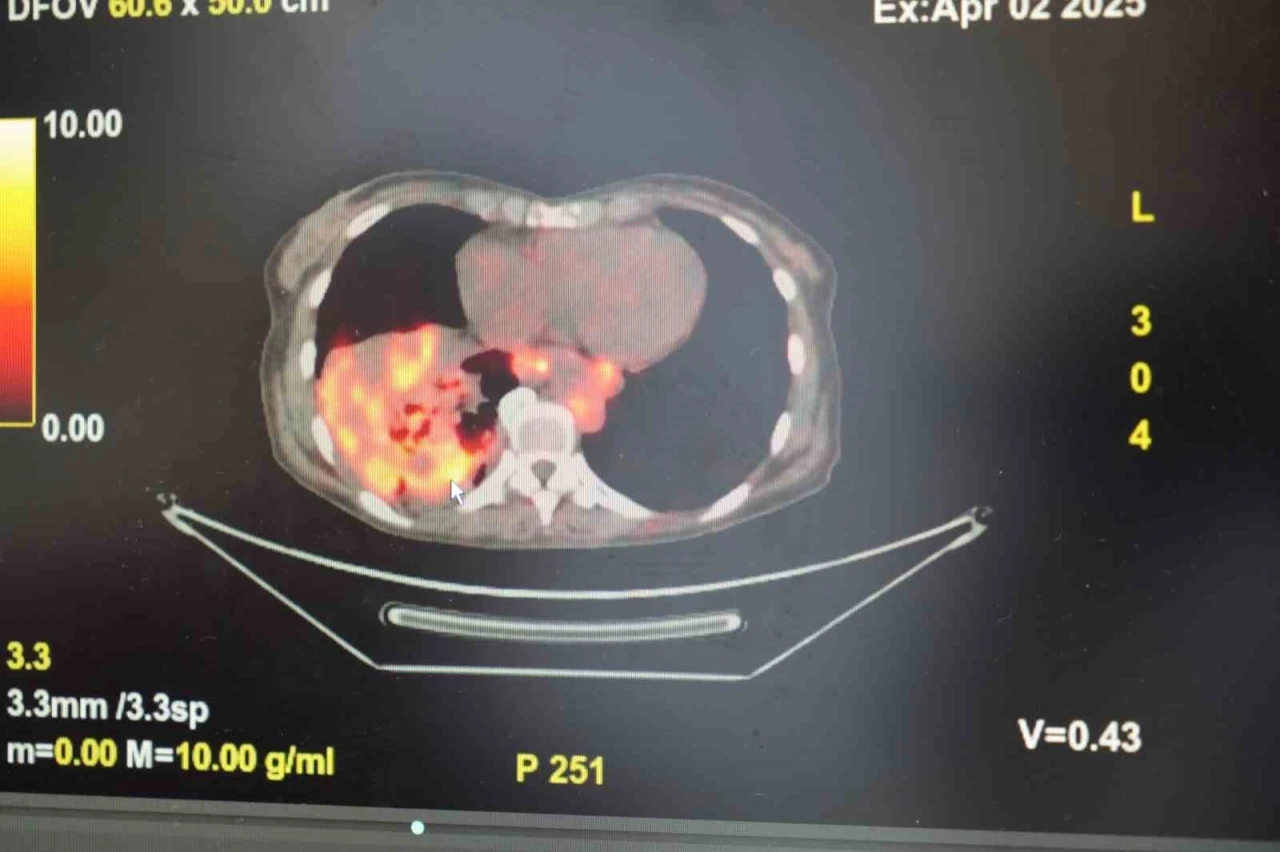

Göğüs Hastalıkları Uzmanı Prof. Dr. Şevket Özkaya, son yıllarda sigara kullanmayan bireylerde de akciğer kanseri vakalarının dikkat çeken bir oranda arttığını belirterek, özellikle kadınlarda görülen adenokarsinom tipi akciğer kanserinin artış gösterdiğine dikkat çekti. Bu konuda yapılan son araştırmalara değinen Özkaya, akciğer kanseri teşhislerinin yaklaşık yüzde 20’sinin hiç sigara içmemiş bireylerde konduğunu söyledi. "Kadınların anatomisi ve bağışıklık sistemi risk faktörlerini artırıyor"

Prof. Dr. Şevket Özkaya, konuyla ilgili yaptığı değerlendirmede, "Hiç sigara içmemiş kadınların akciğer kanserine yakalanma ihtimali, sigara içmemiş erkeklere kıyasla iki kattan fazladır. Kadınlarda daha sık görülen otoimmün hastalıklar ve bağışıklık sisteminin fazla çalışmasına bağlı kronik iltihaplanmalar (inflamasyon) bu riski artırabiliyor. Ayrıca bağışıklık sistemini güçlendirmek için kullanılan bazı ilaçlar, vücuttaki değişimlere karşı aşırı yanıt oluşmasına neden olarak kanser gelişimine zemin hazırlayabiliyor" dedi. "Kadınlar hava kirliliğine karşı daha savunmasız"

Özkaya, kadınların akciğer yapısının da bu duruma katkı sunduğunu belirterek, "Kadınların akciğerleri erkeklere göre daha küçük ve daha dar hava yollarına sahip. Bu da ince partiküllerin (PM2.5 gibi) daha derinlere inerek akciğerde birikmesine neden olabiliyor. Hava kirliliği, ev kimyasalları, iş yerinde maruz kalınan zararlı maddeler, hatta ev içi yemek pişirme dumanları bile riski artırabiliyor" diye konuştu. "Ev içi maruziyetlere dikkat edilmeli"

Prof. Dr. Özkaya, sigara içmeyenlerde artan akciğer kanseri riskinin ardında çok sayıda çevresel faktör olduğunu vurguladı: "Radon gazı, pasif içicilik, odun ya da kömürle ısınan yetersiz havalandırılmış ortamlar, yemek pişirme sırasında oluşan duman gibi unsurlar özellikle ev hanımı olan kadınları tehdit ediyor. Kadınların daha fazla zaman geçirdiği iç mekânlar, hava kirliliğine maruz kalma açısından ciddi bir risk alanı. Bu nedenle, bu gruplar için önleyici stratejiler geliştirmek hayati önem taşıyor" şeklinde konuştu. "Radyasyona maruziyet riski evlerde başlıyor"

Dünyanın en prestijli tıp dergilerinden yayımlanan bir araştırma üzerinde açıklama yapan Prof. Dr. Şevket Özkaya, araştırmaya göre, sigara içmeyenlerde en sık görülen tür olan akciğer adenokarsinomu, kadınlarda akciğer kanserlerinin yaklaşık yüzde 60’ını oluşturduğunu söyledi. Prof. Dr. Özkaya, sigara dışındaki risk faktörlerinin başında radon gazının geldiğine dikkat çekerek, "Radon gazı, evlerimizde farkında olmadan soluduğumuz, renksiz, kokusuz, tatsız ve radyoaktif bir gazdır. Müsaade edilen değerlerin üzerinde solunduğunda akciğer kanseri riskini artırıyor. Radon gazı özellikle taş, toprak ve çimento gibi yapı malzemelerinde doğal olarak bulunuyor. Bu maddelerden ortama sürekli yayılan gaz, solunum yoluyla akciğerlere ulaşıyor" ifadelerini kullandı.